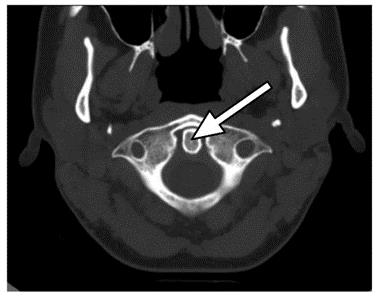

Na zamieszczonym przekroju poprzecznym TK kręgosłupa szyjnego strzałką wskazano

Ilustracja do pytania 32

A. rdzeń kręgowy.

B. otwór kręgu szczytowego.

C. guzek tylny kręgu szczytowego.

D. ząb kręgu obrotowego.